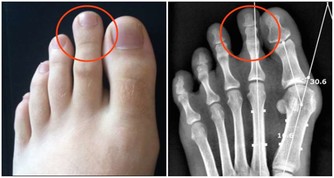

關節痛。關節疼痛主要是由於受涼或者血瘀,經脈閉阻不通所致,採用熱敷,可以起到祛寒通絡止痛的功效。將粗鹽放入鍋中炒熱,直到燙手即可。把炒熱的粗鹽用布包起來。然後把粗鹽熱敷包放在疼痛、畏寒的關節上,每次熱敷15~20分鐘左右。熱敷時墊一條毛巾,以防燙傷。